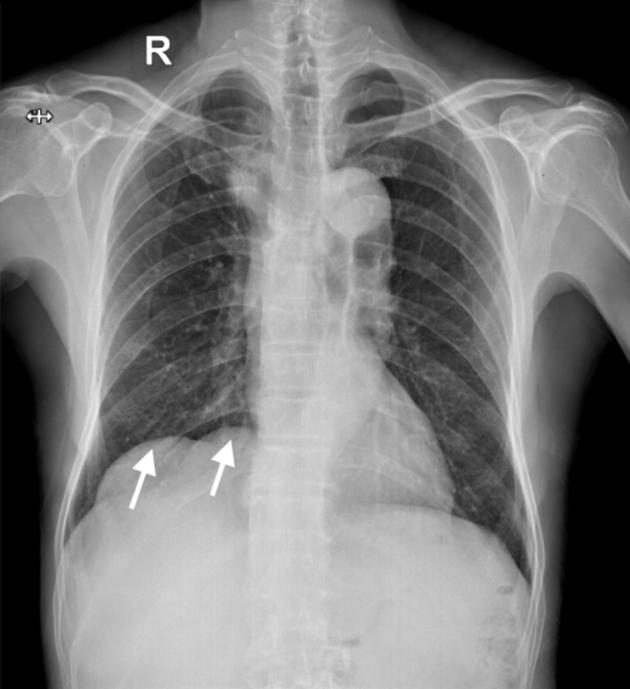

• Echocardiography can demonstrate hepatic cyst–induced right atrial compression. • Hepatic cyst–induced blood flow stasis can cause internal jugular venous thrombus. • Laparoscopic deroofing of hepatic cysts is a safe and effective treatment.

• 超声心动图可显示肝囊肿所致的右心房受压。

• 肝囊肿所致的血流淤滞可导致颈内静脉血栓形成。

• 腹腔镜下肝囊肿去顶术是一种安全有效的治疗方法。